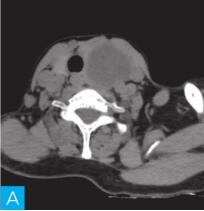

甲状腺CT检查:CT检查设备为256层iCT,病人采取仰卧位,扫描范围自外耳道平面至下颌角以下,常规扫描层厚为0.9mm、层间隔0.9mm,电压120kV,管电流280mA,矩阵512×512;经右肘静脉团注法增强扫描,碘海醇80ml,流速4ml/s,动脉期25秒扫描,静脉期60秒扫描。见图1。

图1 甲状腺CT

A、B.甲状腺CT横断面平扫;C~H.甲状腺CT横断面增强

答案A 解析:甲状腺左叶病变边界清楚,形态较规则,密度不均匀,部分为实性改变,部分为囊性灶,其内可见斑点状粗大钙化灶,气管及食管向右推移,左侧颈总动脉向左后推移,胸锁乳突肌向左前推移。根据表现病变不是单纯囊性病变。

CT平扫可见甲状腺左叶圆形以低密度为主病灶,大小为8.0cm×6.5cm,边界清晰,边缘尚光整,其内密度不均匀,低密度区CT值18HU,部分密度稍高,并可见斑点状粗大钙化影;CT增强后,甲状腺左叶病变呈不均匀渐进性强化,结节状改变,动脉期强化区CT值99HU,静脉期CT值85HU,且强化范围增大,提示该病变的血供较为丰富,应该考虑肿瘤样病变,结节性甲状腺肿可能性大。